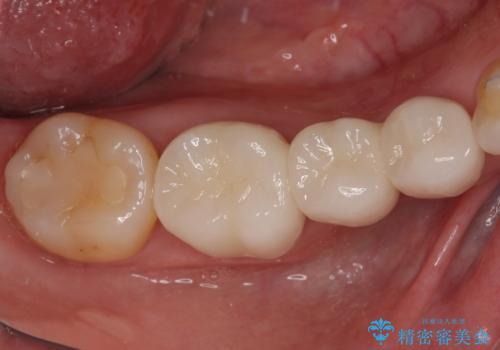

右下の欠損分は奥歯が倒れ込んでスペースがなくなっていたため、矯正治療により本来の位置に歯を移動させ、オールセラミックブリッジによる欠損補綴治療を行うこととしました。

右下は移動量が多いため、十分な移動が達成されない場合はワイヤー装置を使用する予定としておりましたが、しっかりとマウスピースを装着してくださったため、前歯とともに十分に歯を動かすことができました。